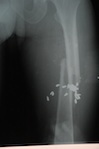

Medical 8-05 to 6-06

Koza Medical